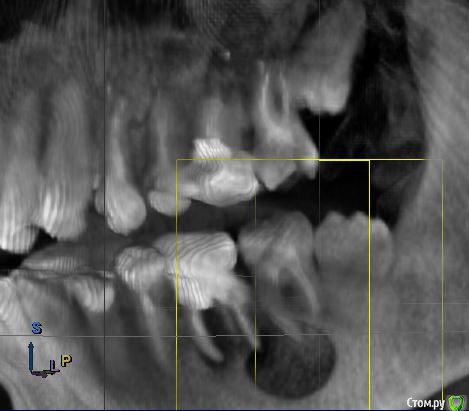

Anna275 Опубликовано 18 октября, 2018 Поделиться Опубликовано 18 октября, 2018 Здравствуйте! Несколько дней назад мужу диагностировали на КТ радикулярную кисту в нижней челюсти слева. Врач учреждения, где делали КТ, расписал следующий план лечения: удаление трех зубов (6-ка, 7-ка, 8-ка), цистоэктомия, костная пластика челюстно-лицевой области (замещение костного дефекта или заполнение биоактивным материалом), применение препарата PRF (2 пробирки). Ну и в дальнейшем установка имплантов. Мы пока пребываем в шоке, уже три дня читаю интернет, записались на пару консультаций в разные клиники, но пока время не подошло; параллельно решила попросить совета на этом сайте. Уважаемые стоматологи, вы согласны с тем, что требуется удаление аж трех зубов??? Консервативное лечение в нашем случае уже никак? Для информации - в 6-ке стоит штифт.Прошу прощение за техническую неподкованность, прикрепляю копии снимков, если нужно (и можно на этом сайте - могу выложить результаты КТ в формате iso). Заранее спасибо! Ссылка на комментарий

DmitrySH Опубликовано 18 октября, 2018 Поделиться Опубликовано 18 октября, 2018 Шестой - 100% удаление из за сильного разрушенияВосьмой - удаляется из-за своей не функциональности Седьмой - сам по себе не так плох, можно и попытаться сохранить, только это усложнит и растянет всю работу Удаление трех сразу и имплантация -более прогнозируемо Ссылка на комментарий

red_butler Опубликовано 19 октября, 2018 Поделиться Опубликовано 19 октября, 2018 Перелечить седьмой. Убрать шестой (без вариантов) на сколько получится вычистить оболочку кисты через лунку. Через пару тройку месяцев принимать решение о цистэктомии. Восьмой убрать до протезирования седьмого.P.s. на верхней челюсти два кандидата на удаление 1 Ссылка на комментарий

kriokov Опубликовано 19 октября, 2018 Поделиться Опубликовано 19 октября, 2018 1 этап удалил бы три зуба , 6, 7, 8, с одномоментной цистэктомией (удаление кисты) через лунки удаленных зубов, никакие бы костные заменители для восстановления дефекта на первом этапе не применял.(дефект маленький , наружная кортикальная везде почти целая, заживет сам)2. через 6 месяцев повторно клкт этой зоны, с целью решения вопроса о возможности установки имплантатов и необходимости "костной пластики" 1 Ссылка на комментарий

Bier Опубликовано 20 октября, 2018 Поделиться Опубликовано 20 октября, 2018 Если хочется максимально спасать зубы, то 7й можно перелечить. 6й однозначно удаляется.в 8м смысла нет. Ссылка на комментарий